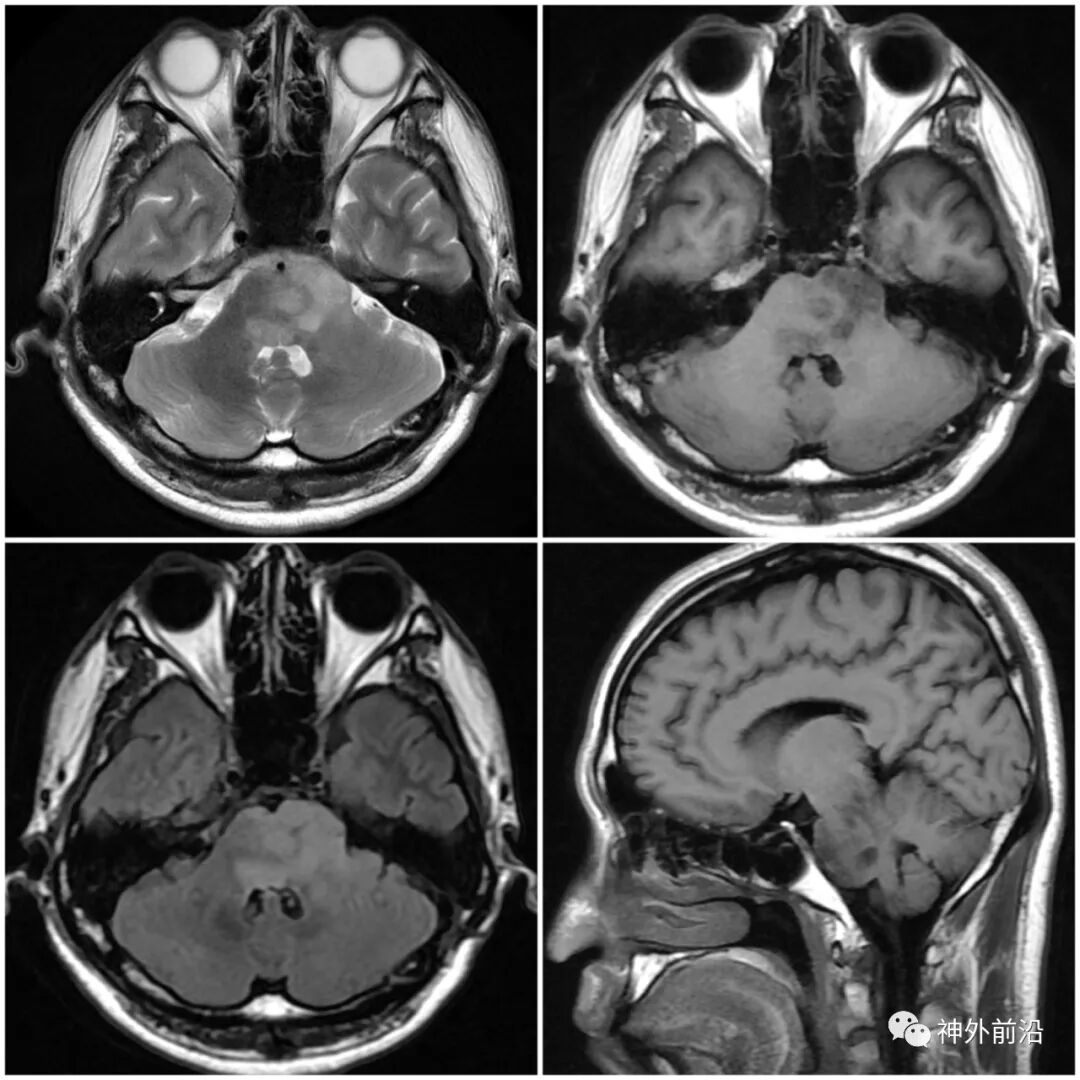

脑干弥漫性中线胶质瘤一例武汉高尚医学影像